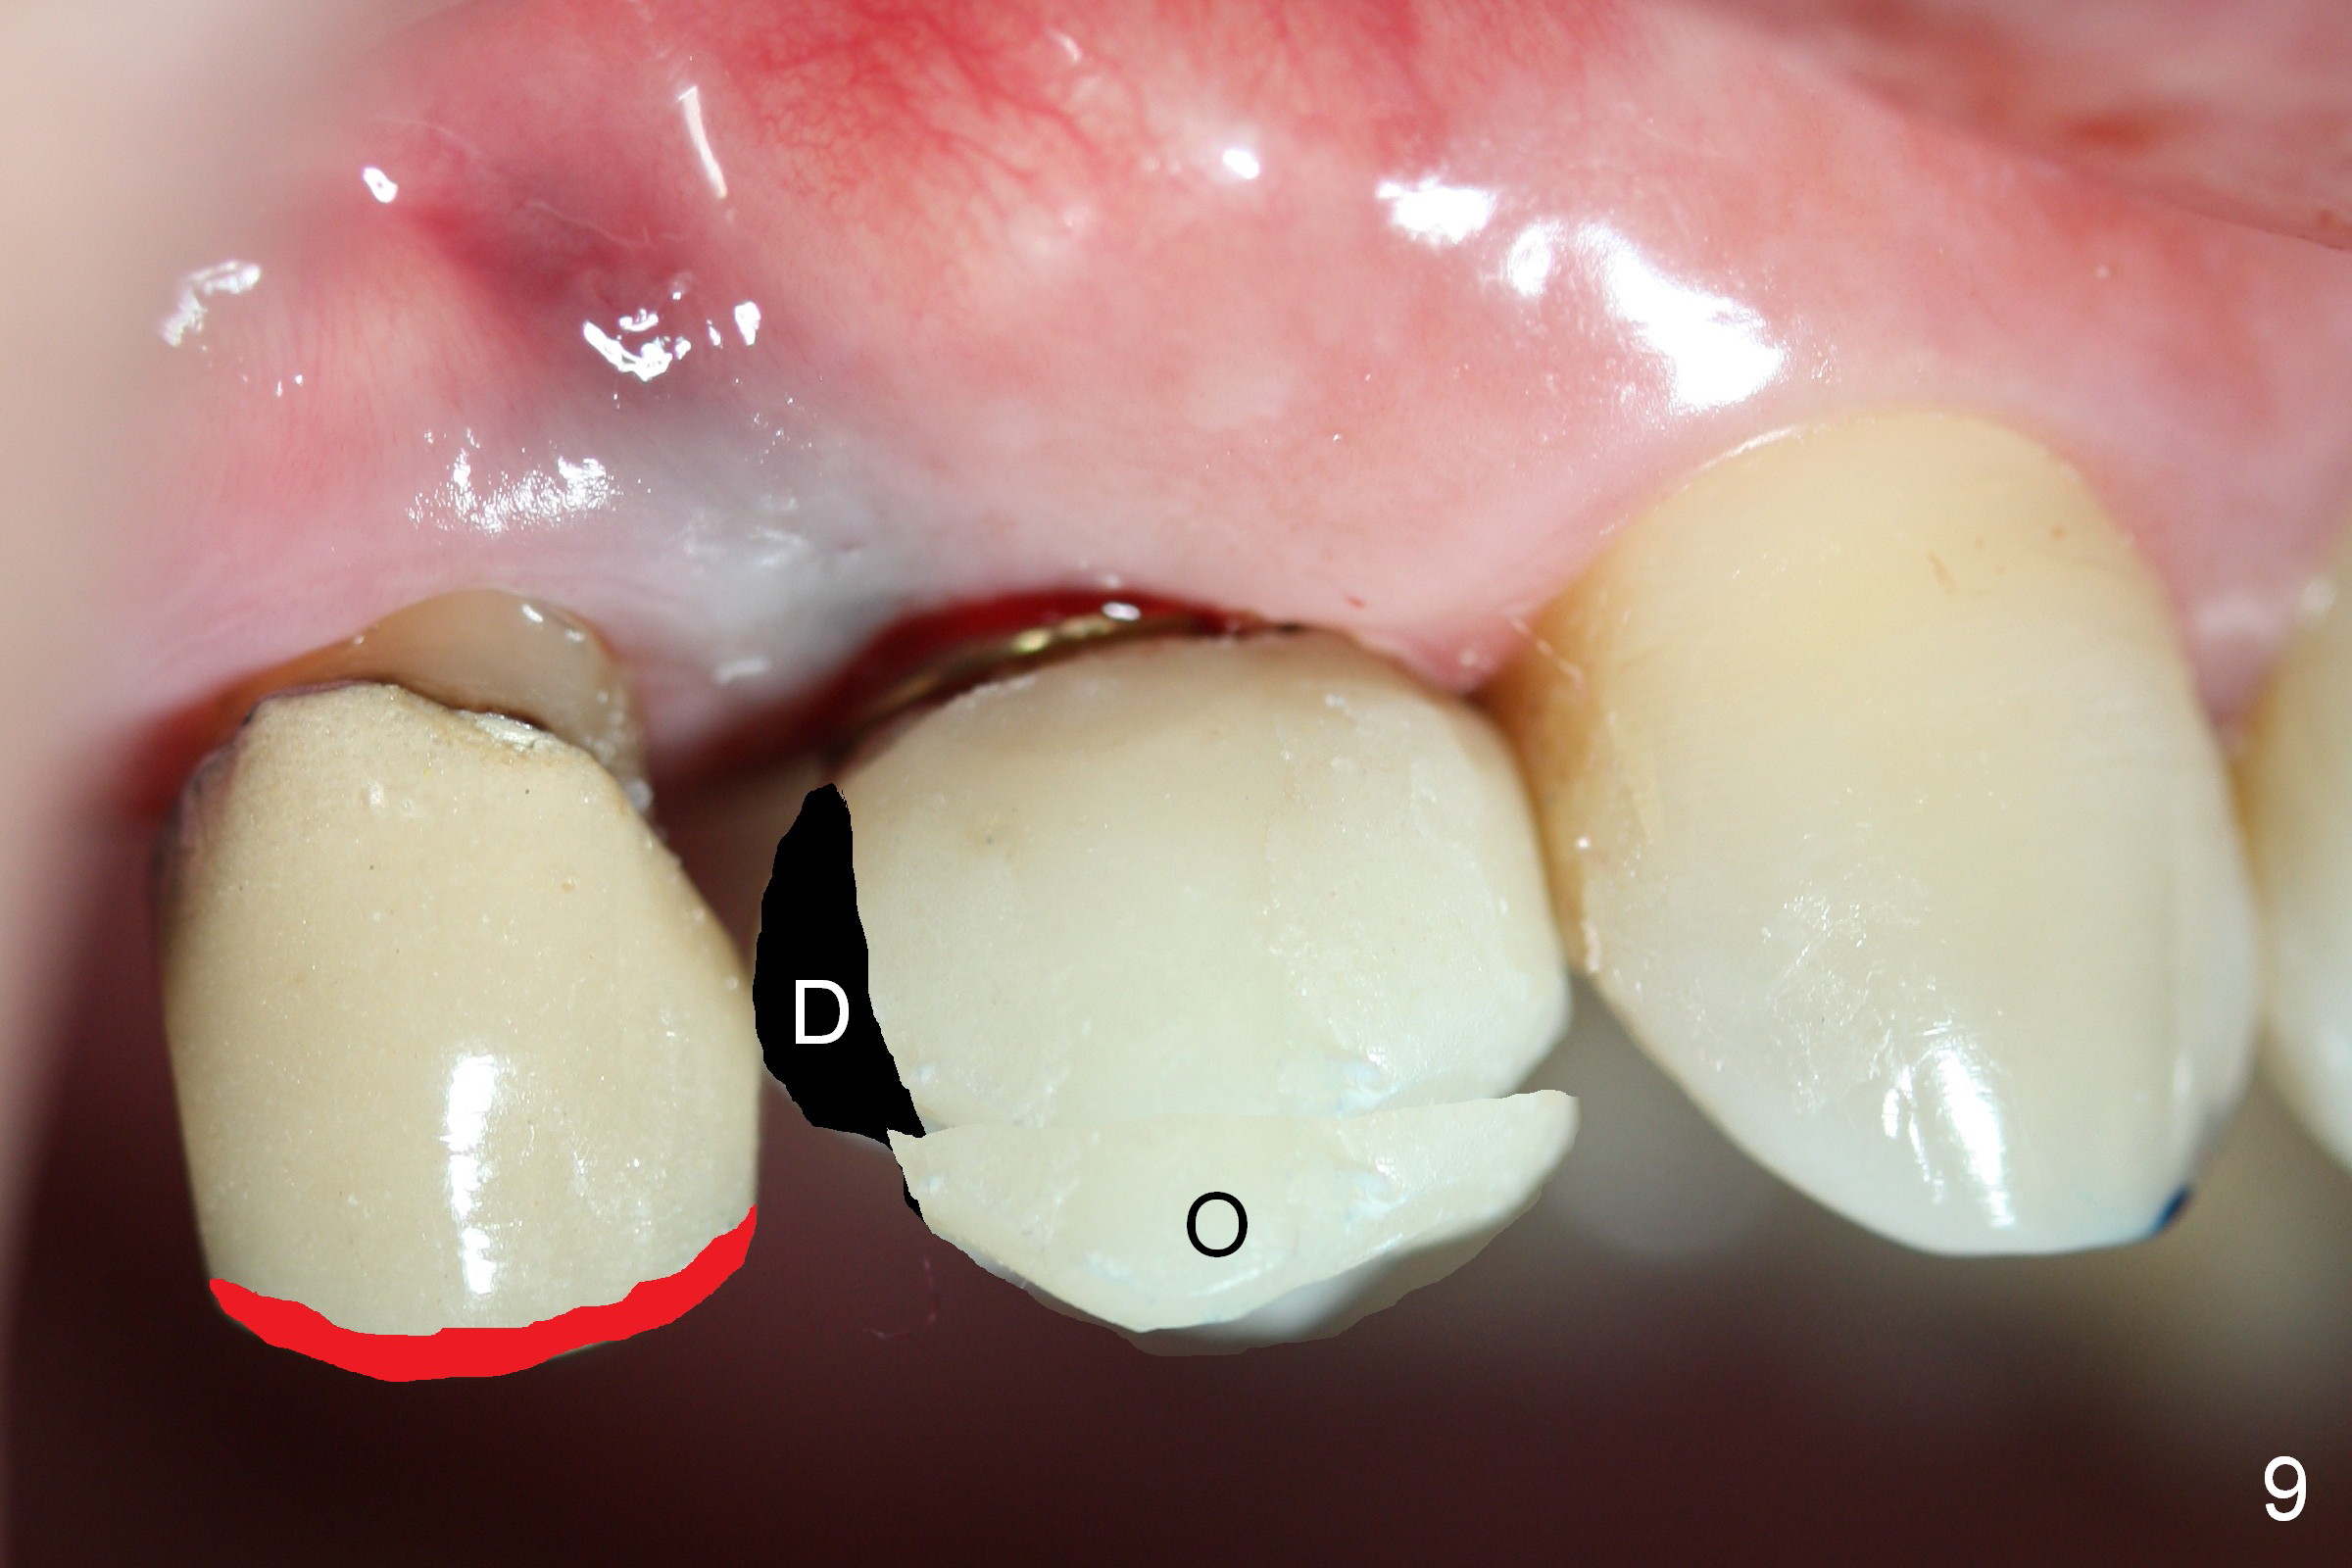

The distal surface of the provisional will be reduced (Fig.9,10 D), whereas the occlusal surface will be increased (Fig.9 O). If needed, the occlusal surface of the distalized tooth #4 will be reduced (Fig.9 red area) so that there is no interference for tooth to move. Hooks will be placed on the buccal and lingual surfaces of the provisional (Fig.10 green curved lines). Power chains will be placed on the hooks and wrapped around the tooth #4. In due time, the tooth will be mesialized (Fig.11 arrow). Implants at the sites of #2 and 3 will be placed in more appropriate positions.